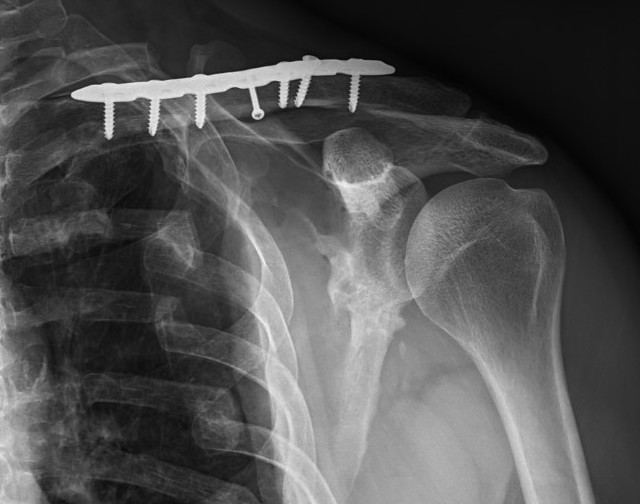

ORIF clavicle

Minimally displaced glenoid fracture

Scapular neck fracture with clavicle fracture